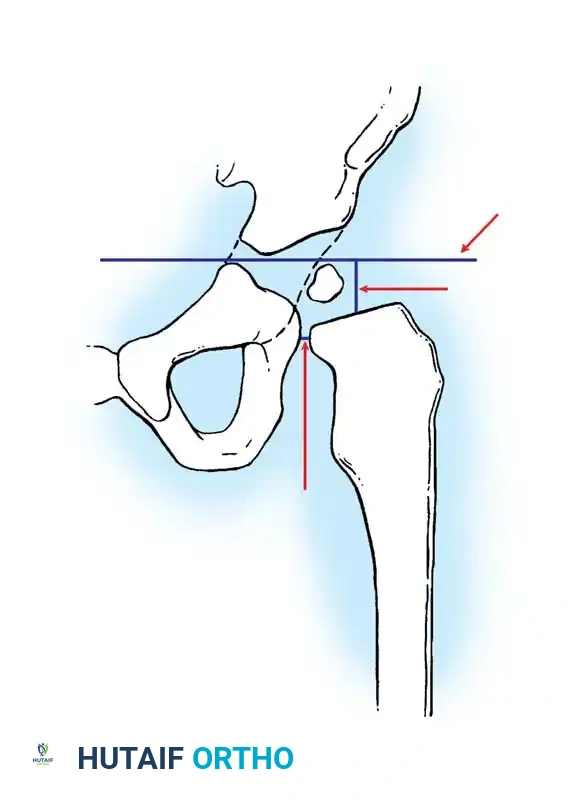

Radiography: Becomes reliable after 4 to 6 months as the ossific nucleus of the femoral head appears. Key radiographic parameters include:

* Hilgenreiner's Line: A horizontal line through the triradiate cartilages.

* Perkins' Line: A vertical line dropped from the lateral margin of the acetabulum, perpendicular to Hilgenreiner's line.

* Shenton's Line: A continuous arc drawn from the medial border of the femoral neck to the superior border of the obturator foramen. Disruption indicates proximal migration.

* Acetabular Index: The angle between Hilgenreiner's line and a line drawn from the triradiate cartilage to the lateral edge of the acetabulum. Normal is <30 degrees in newborns; >35 degrees is highly suspicious for dysplasia.

Radiographic evaluation: Normal hip anatomy (left) versus Dysplastic hip anatomy (right) demonstrating disruption of Shenton's line and an increased acetabular index.

Diagrammatic representation of the Salter Innominate Osteotomy. Note the complete iliac cut and the placement of the triangular bone graft to redirect the acetabulum.